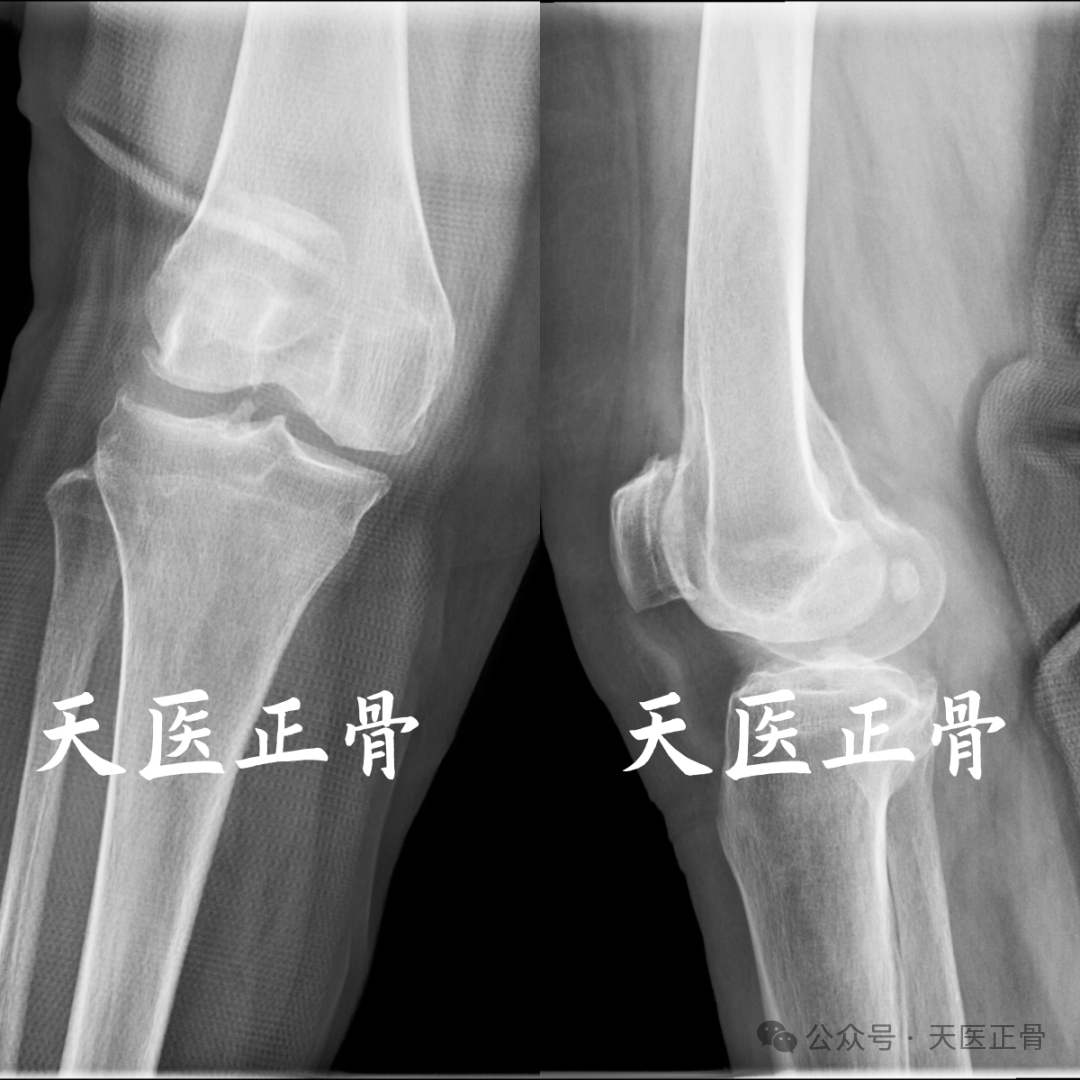

髌骨脱位是髌骨在活动中脱离股骨滑车凹的膝关节损伤疾病,可分为复发性髌骨脱位和创伤性髌骨脱位,常见的创伤性髌骨脱位为髌骨外侧脱位,偶尔可以见到关节内脱位、垂直脱位现分享1例髌骨关节内水平旋转脱位病例。

患者女,62岁,下蹲时摔倒致患肢功能障碍活动受限,于我院就诊,诊断为髌骨脱位。

复位前影像如下:

根据本例MR的图像可以证实髌骨上极骨赘嵌顿于髁间窝导致髌骨关节内嵌顿的假设,从而引起髌骨关节内水平脱位。